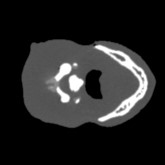

Cone-beam CT (CBCT) employs a flat-panel detector to achieve three-dimensional imaging with high spatial resolution. However, CBCT is susceptible to scatter during data acquisition, which introduces CT value bias and reduced tissue contrast in the reconstructed images, ultimately degrading diagnostic accuracy. To address this issue, we propose a deep learning-based scatter artifact correction method inspired by physical prior knowledge. Leveraging the fact that the observed point scatter probability density distribution exhibits rotational symmetry in the projection domain. The method uses Gaussian Radial Basis Functions (RBF) to model the point scatter function and embeds it into the Kolmogorov-Arnold Networks (KAN) layer, which provides efficient nonlinear mapping capabilities for learning high-dimensional scatter features. By incorporating the physical characteristics of the scattered photon distribution together with the complex function mapping capacity of KAN, the model improves its ability to accurately represent scatter. The effectiveness of the method is validated through both synthetic and real-scan experiments. Experimental results show that the model can effectively correct the scatter artifacts in the reconstructed images and is superior to the current methods in terms of quantitative metrics.